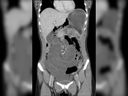

Doctors performed an upper gastrointestinal endoscopy – when a tiny camera at the end of a long, flexible tube is fed orally into the upper digestive system – and found the many-legged squatter.

“For the last two-three days, the patient was suffering from indigestion and bloating after eating food. It was during routine inspections that we incidentally spotted the cockroach,” senior gastroenterological consultant Dr. Shubham Vatsya told the Express, noting to The New India Times that it may have crawled in while the man slept.

Faced with the “life-threatening situation,” Vatsya and his team performed a 10-minute endoscopic procedure to evict the uninvited guest.

“We activated the suction button on the scope, effectively sucking the cockroach into the suction channel, leading to its removal from the body and saving the man’s life,” Vatsya told the Express.